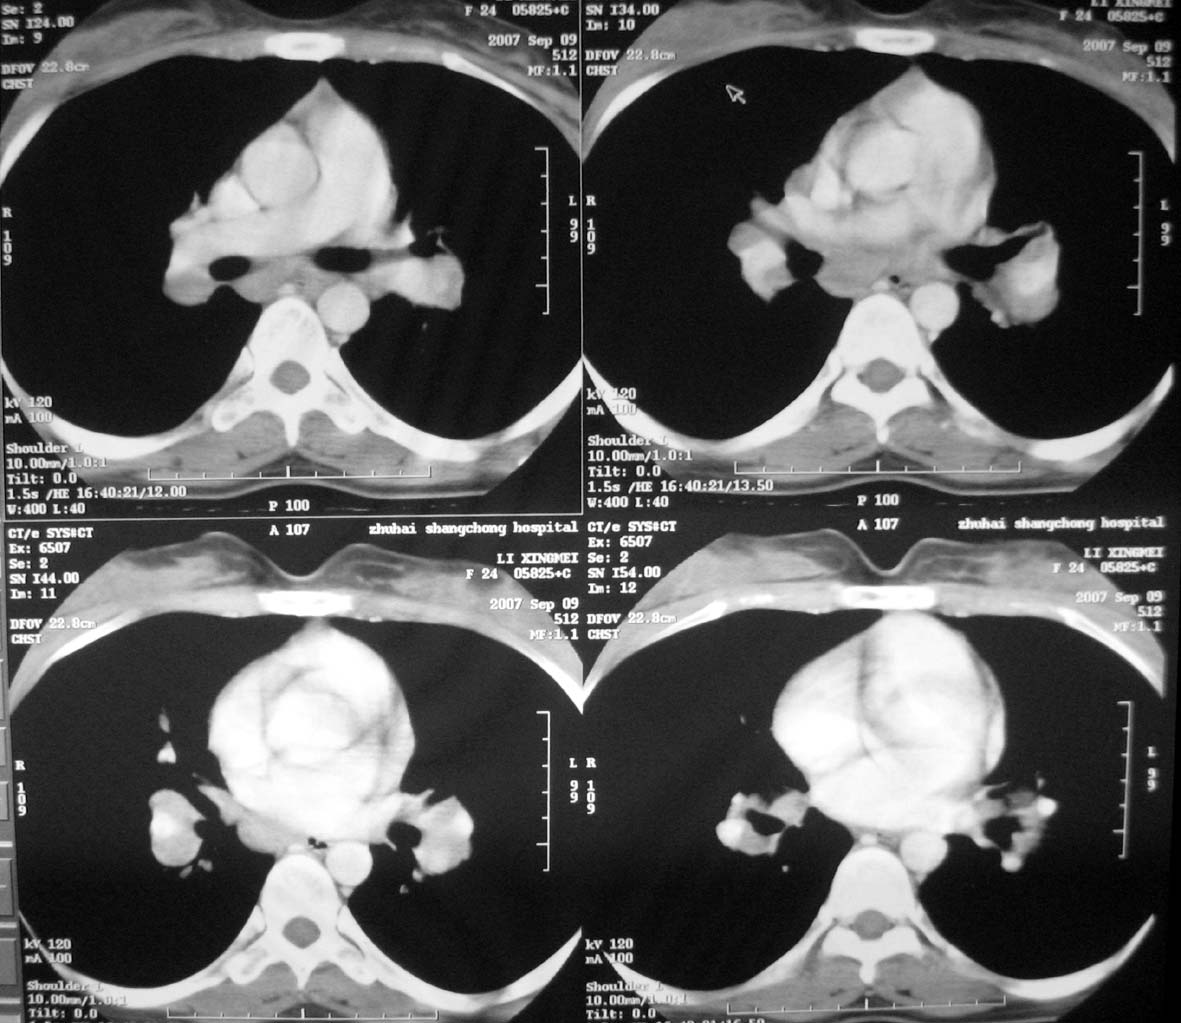

以下是引用qiuleiyu在2007-9-14 19:12:00的发言:[br]纵隔(气管旁组\\隆突下\\主动脉旁组\\血管前组)及肺门淋巴肿大,边界欠清.密度均匀,内无明确钙化.[br]结合临床症状考虑;结节病可能大.[br]鉴别;1,淋巴瘤,可有全身浅表淋巴肿大,肝脾大,发热等.肿大淋巴主要为气管旁组及血管前组及主动脉旁组,肺门肿大不明显.典型者为冰冻纵隔.[br] 2,转移瘤;多见于肺癌,按淋巴链分布肿大,单侧肿大多见,常可见坏死.[br] 3,castlemans;增强后明显血管样强化.内部可有分支状钙化,蜘蛛状瘢痕.周边可有粗大血管.[br] 4,结核;67%有肺部结核灶,肿大淋巴结节,内部可有钙化,增强环状或分格样强化.